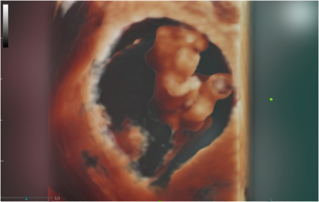

Ultrasound Journal 34 - Use of IOTA-ADNEX & O-RADS risk assessment models in MDT management of Adult Granulosa Cell Tumor

Comprehensive overview of granulosa theca cell tumors of the ovary, covering epidemiology, clinical presentation, diagnosis, treatment options, and prognosis for both adult and juvenile types.